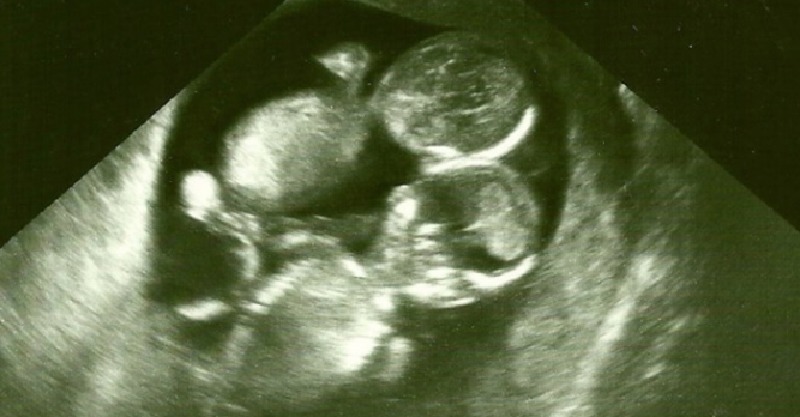

正當凱特喜出望外,醫生卻發現了另一個沉重事實,凱特所懷的雙胞胎是機率只有1%的「MoMo寶貝」,也就是「單羊膜雙胞胎」,這樣的雙胞胎因為共用一個羊膜,胚胎極有可能會發展成連體嬰,也容易因為沒有薄膜隔閡造成臍帶纏繞,導致胎兒缺氧的狀況,存活率只有正常雙胞胎的一半,正因如此,醫生建議凱特先不要對外公開懷孕消息。

生產這天總算到來,凱特和家人抱著既期待又害怕的心情進入醫院,當醫生替她剖開孕肚後,發現了這驚喜的一幕!這對雙胞胎雖然臍帶彼此互纏,卻沒有阻礙到寶寶生長,兩位女嬰都奇蹟活了下來!